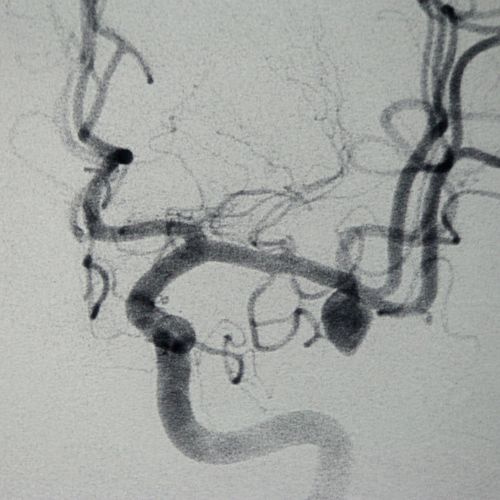

Aneurismas Cerebrales

También conocido como aneurisma intracraneal o intracerebral, es un punto débil o fino en un vaso sanguíneo cerebral que sobresale como un balón y se llena de sangre.